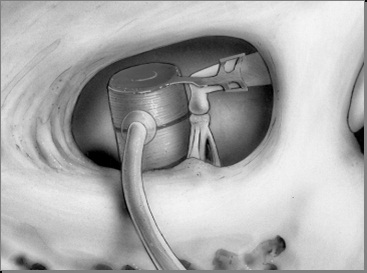

A vevő-stimulátor van rögzítve subperiosteally.

Miután az implantátum csonthártya lebeny van rögzítve a helyén varratokat a széle a műszerfal és a csonthártya. lágyszövet metszést összevarrtuk rétegekben. bőr varrás lehet twining kerek, csomópont, intradermális. (6. ábra)

6. ábra - Layered sebvarró, varrat